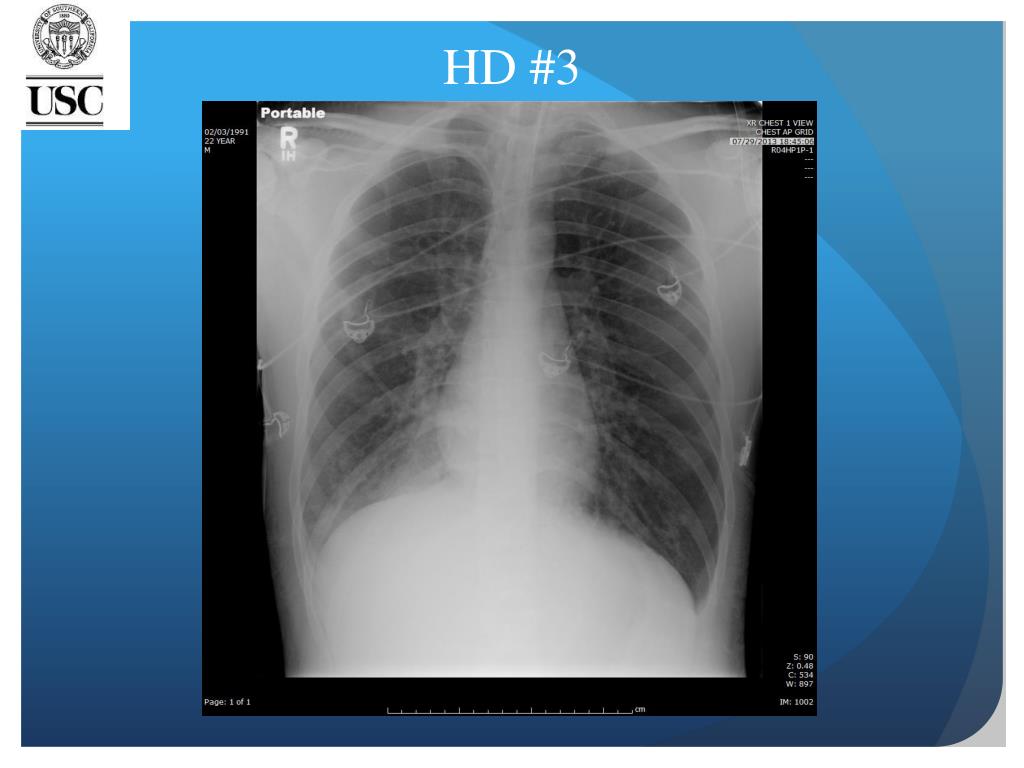

23. HD #3